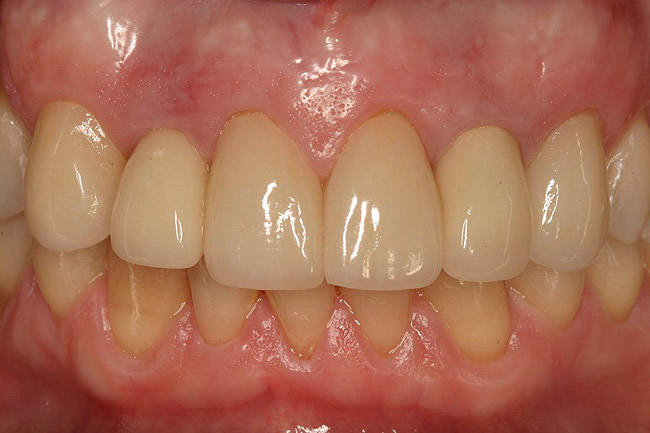

Figure 4  Final restoration of implants in the Nos. 8 and 9 sites 3 years after placement. Note the short central papilla regardless of the presence of bone. Restoration courtesy of Dr. Alan Goldberg.

Figure 4

Figure 8  The post-implantation and post-restoration view shows esthetically pleasing, symmetric crowns and mucosal contours, with the Nos. 7 and 10 implant prostheses blending in imperceptibly with the natural dentition. Restoration courtesy of Dr. Jeffrey Warren.

Figure 8